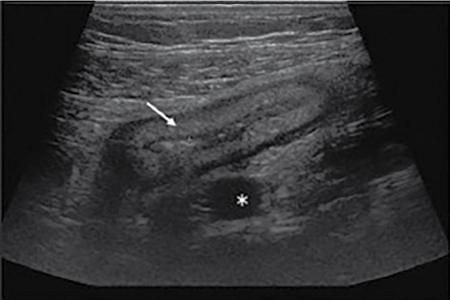

Ultrasonography (USG)

Kulbir Ahlawat, Ravi Chaudhary, Arvind Pandey, Anuj Bahl, Navni Garg, Sonam Shah, Sonali Sharma EMBRIOLOGY AND ANATOMY OF COLON Sonali Sharma A deep understanding of the development and the embryology of the colon is essential to understand the variety of the developmental anomalies related to the aberrations in the normal embryological processes (Table 8.4.1.1). Broadly the development of the colon can be summarized in three stages: The rate of growth of the embryo exceeds the growth rate of the yolk sac during the third and the fourth weeks of development. During the fifth week there is development of the omphalomesenteric duct or the Vitello intestinal duct or the yolk stalk which serves as a connection between the extraembryonic and the intraembryonic coelom (Fig. 8.4.1.1). The midgut at this point is divided into two equal length segments and the loop has its axis at the superior mesenteric artery (SMA). The apex is marked by the yolk stalk or the omphalomesenteric duct. There is a periarterial segment and the postarterial segment of the loop, the former starting at the foregut–midgut junction and ending at the apex. The postarterial segment lies between the apex and the midgut–hindgut junction. Eleventh week marks the beginning of the return of the postarterial segment of the gut, which continues to rotate in front and then to the right of the SMA. By the twelfth week the colon completes a 270-degree anticlockwise rotation with prior 90 degrees during herniation, and a further 180-degree counterclockwise rotation during the reduction of the postarterial segment. The prearterial segment gives rise to: Postpapillary duodenum, jejunum, ileum (major part) The postarterial segment gives rise to: Terminal ileum, caecum, appendix, ascending colon, transverse colon (major part) There is a switch over to the hind gut at the junction of the proximal two-thirds and the distal one-third of the transverse colon where there is also a switch over in the arteries supplying the segments, with SMA (middle colic) supplying the proximal segment and the inferior mesenteric artery (IMA, left colic) supplying the distal segment. The fifth week also marks the development of a small swelling in the proximal postarterial segment which represents the caecal bud. There is the herniation of the midgut at the sixth week of development called the physiological herniation of the gut. At this time there is growth of the liver, and the right lobe pushes the prearterial segment downwards and to the right. The series of events represent a 90-degree counterclockwise rotation when viewed enface (Fig. 8.4.1.2). The anomalies of this stage (stage of physiological herniation) are rare and include situs inversus, inverted duodenum and extroversion of the cloaca. With growth of the peritoneal cavity and no further significant growth of the liver, there develops a free space within the peritoneal cavity for the reduction of the midgut hernia at about the tenth week of development. Eleventh week marks the beginning of the return of the postarterial segment of the gut, which continues to rotate in front and then to the right of the SMA. By the twelfth week the colon completes a 270-degree anticlockwise rotation with prior 90 degrees during herniation, and a further 180-degree counterclockwise rotation during the reduction of the postarterial segment (Fig. 8.4.1.2). There occurs the fixation of the gut in this final sequence of events which start towards the later part of the first trimester. Anomalies of the reduction phase of the physiological hernia are relatively more common than the ones that originate from the stage of physiological hernia and include nonrotation, malrotation, reversed rotation, internal hernia and omphalocele (Fig. 8.4.1.3). There is a discrepancy in the growth rates of the base of the caecum and the apex of the caecum which leads to the formation of an appendage called the appendix. Further till the fifth month of gestation there is a progressive gradual resorption of the dorsal mesentery. Gradually, fusion of parts of the primitive mesentery occurs, with fixation of the duodenum, and the ascending and descending parts of the colon to the posterior abdominal wall in their final position. Anomalies of this stage of fixation are common and include mobile caecum, subhepatic or undescended caecum, hyperdescent of the caecum and persistent colonic mesentery (Fig. 8.4.1.3). The mesentery of the transverse colon (mesocolon) persists with its partial fusion with the greater omentum leading to the formation of the gastrocolic ligament. The distal end of the transverse mesocolon condenses to form the phrenicocolic ligament, which suspends the transverse colon near the splenic flexure fixing it to the diaphragm in the left upper abdomen. It also prevents the spread of pathologies from the left paracolic gutters to the left upper abdomen. The sigmoid colon continues to maintain it dorsal mesentery or sigmoid mesocolon at its posterior aspect. The length of the mesentery is short relative to the variable length (sometimes very long) of the colon to which it is attached. This discrepancy leads to the sigmoid volvulus. Colon is formed from the midgut and the hind gut with the junction of the proximal two-thirds and distal one-third of the transverse colon being the point of demarcation between the two. The midgut development continues beyond the opening of the papilla, to form the duodenum beyond the papilla, ascending colon and the proximal two-thirds of the transverse colon. This segment is supplied by the Superior Mesenteric Artery with corresponding venous and lymphatic drainage (Fig. 8.4.1.4). The distal third of the transverse colon, descending colon, sigmoid colon, rectum and the anal canal above the dentate line all are derived from the hind gut and supplied by the Inferior Mesenteric Artery with corresponding venous drainage and lymphatics (Fig. 8.4.1.3). Enteric nervous system (ENS) functions independent of the CNS and is thus referred to as the ‘Second Brain’ and it regulates many aspects of gastrointestinal physiology including peristalsis, sphincter tone, glandular secretions, smooth muscle activity and microcirculation. The neuroenteric ganglion cells migrate from the neural crest to the upper end of the alimentary tract and then follow vagal fibres caudad during the first trimester. The ENS is composed of two types of ganglionated plexuses: the Auerbach (myenteric) plexus, which is located in the outer muscular layer and regulates gastrointestinal tract motility and function of extraluminal organs, and the Meissner (submucosal) plexus, which regulates enteral secretory activity. In contrast to the neural crest-derived cells of the enteric plexuses, interstitial cells of Cajal (ICCS), which serve as the ‘pacemakers of the intestine’, arise from intestinal mesenchyme. Sympathetic innervation: L2–L5 roots, inferior and superior mesenteric plexus and coeliac ganglia. Parasympathetic innervation: The Vagus nerve and sacral spinal cord (S2–S4 spinal nerves). Great details of the various disorders are beyond the scope of this book. A short review is written (Table 8.4.1.2). Duodenal atresia (11%) – most common Meckel’s diverticulum (11%) – second commonest Omphalocele (9%) Other stenosis or atresia (5%) Hirschsprung’s disease (2%). Cardiac and orthopaedic anomalies Biliary atresia Pancreatic anomalies Microcolon Esophageal webs Tracheoesophageal fistula It is commonly known as malrotation and occurs due to an arrest of the first 90 degrees rotation of the midgut which causes the prearterial segment to lie to the right of the hernial sac and SMA and the postarterial segment to the left. The dorsal mesentery lies in the midline and is shared by both the pre and the postarterial segments. This makes the bowel loops imbalanced and mobile and prone to volvulus. The twisting of the midgut loop can occur mostly at the level of the duodenojejunal junction and less commonly at the level of the midtransverse colon. There is a disruption of the normal SMA to SMV relationship, with the SMV seen to the left of the SMA in this pathology. In this there is a reversal of the sequence of return of the midgut with postarterial segment returning first and lying posterior to the SMA with the duodenum and the small bowel lying anterior to the colon. Abnormal mesenteric bands may form leading to obstruction. Failure of the midgut to retract into the abdominal cavity with retention in the hernial sac. The colon may fail to complete its final 180-degree rotation and lie in the right upper quadrant. Incomplete resorption of the mesentery may lead to abnormally mobile colon segments due to centrally placed dorsal mesentery. It is interesting to know that the rotation anomaly of the prearterial segment may be an isolated entity but, the rotation anomaly of the postarterial segment is invariably associated with the anomaly of the prearterial segment. Caecum is an intraperitoneal organ either almost completely invested with peritoneum or at least invested by it in its lower half. It is fixed by a small mesocaecum. In 5% individuals the caecum rests directly on the iliacus muscle and the psoas major muscle due to lack of the peritoneum. Also, an abnormally mobile caecum and ascending colon may be seen in about 10%–22% individuals usually due to a long mesentery. Thus varied locations of the caecum may be seen. This is a fixation anomaly and may lead to a volvulus. This exclusively affects the postarterial segment with normal mobility and position of the prearterial segment. The caecum may lie in the left upper quadrant. Errors in the resorption of the dorsal mesentry, may lead to development of abnormal fossae through which the loops of the bowel may herniate (Fig. 8.4.1.5). Few common ones are detailed below: It formed the incomplete fusion of the mesentry of the descending colon. The bowel loops may herniate under the colon and in front of the IMA. This leads to the left paraduodenal internal hernia. A defect in the small bowel mesentery leads to herniation of the loops in the left upper quadrant, beneath the SMA to the right. This is called the right preduodenal hernia and is less common the left preduodenal hernia. Work on the anatomy of the colon dates back to the 16th century with the pioneering work of Andreas Vesalius. The versatile and ever evolving radiological procedures have further added to this knowledge over the past few decades, improving our understanding of this organ. There are no two opinions on the vital functions of absorption of nutrients, water and electrolytes and transmission and storage of residue performed by this organ. The colon is a long tubular conduit with variable length in different individuals, measuring approximately 120–200 cm (Table 8.4.1.3). Large bowel is differentiated from the small intestine structurally due to its unique longitudinal muscular bands called taenia and characteristic macroscopic saccular appearance and haustral pattern and Appendices Epiploic (Fig. 8.4.1.6). The saccular appearance is attributed to the shorter length of the longitudinal muscle fibre bands or taenia, which are about one-sixth shorter in length than the length of the colon per se. Also the haustral pattern or segmented appearance seen in the colon is characteristic, wherein the haustra are separated by the semilunar cresentric incomplete folds known as plicae semilunaris which may be better visualized when appropriate colonic distension is obtained by barium or air insufflation. The colon also has circumferential folds extending around the luminal surface called the plicae circularis, also seen in the small intestine where they represent folds of the mucus membrane. Thus, the plicae circularis are not exclusive to the colon. The longitudinal muscle bands called the taenia coli run along the serosal surface of the colon, and arrange into three muscle bands namely taenia liberis, taenia omentalis and taenia mesocolica, that are located 120 degrees from each other, and run from the caecum to proximal rectum. Taenia omentalis runs posterolaterally and is attached to greater omentum, taenia mesocolica runs posteromedially and is attached to mesocolic taenia and taenia liberis is boundless and runs anteriorly. At the rectosigmoid junction, taenia expands to cover the rectum. At the level of the sacral promontry there is gradual transition between the colon and the rectum, with confluent muscle fibres giving the rectum a Taenia Free appearance. It is worthwhile here to mention briefly the Appendice epiploicae which are exclusive to the colon and not seen in the small intestine as well as rectum and beyond. These are fatty appendages which perform the fat storage reserve function and are located along the serosal surface of the colon. Inflammation of these is now a disclosed entity frequently encountered in the radiological practice. The colon is divided into the caecum including the vermiform appendix, ascending colon, transverse colon, descending colon and the sigmoid colon (Fig. 8.4.1.7). The ascending colon and the descending colon are retroperitoneal, while the caecum, transverse colon and the sigmoid colon are intraperitoneal. The caecum is the widest part of the colon measuring 7.5 cm in diameter while the sigmoid colon is the narrowest part measuring 2.5 cm. It is due to this reason that the caecal masses acquire a very large size before causing obstructive symptoms and present later in the course of disease while the sigmoid colon masses present earlier in the course of the disease with obstructive symptoms. At the posteromedial aspect of the caecal wall two elliptical folds form the orifice for the ileocaecal valve which is formed by the circular muscle layers of terminal ileum and has a typical nipple like appearance. Some authors have suggested that an intact ileocaecal valve is advantageous in patients of short bowel syndrome by increasing the absorption of the nutrients. The ileocaecal valve appears mostly incompetent on the Barium Enema. However, a competent valve is known to prevent colonic decompression in patients of high-grade colonic obstruction. The Vermiform Appendix is a blind-ended tubular appendage arising from the caecal wall at its base posteromedially. It lies mostly intraperitoneally (95%). It is more commonly directed medially towards the ileum, retro caecally or alternatively in the lesser pelvis. Apart from these commonest locations, the appendix may be subcaecal (31%), transverse retrocaecal (2%), paracaecal, preileal (1%) and ascending paracaecal retroileal/postileal (0.5%). Appendix lacks taeniae, haustra, plicae semilunaris and appendices epiploicae and is located at the site of confluence of the three taenia. The appendix can be variable in length ranging 2–20 cm. It is interesting to note that clinically an intraperitoneal appendix is more symptomatic due to inflammation of the parietal peritoneum as opposed to a retrocaecal appendix. The ascending colon is short measures 10–20 cm and lies within the anterior pararenal space. The ascending colon is a (secondarily) retroperitoneal structure covered only on its ventral and lateral surfaces by the posterior peritoneum, with the mesocolon fused with the retroperitoneum. The ascending mesocolon is not a real mesentery because it is not formed by two peritoneal layers suspending the colon. The ascending mesocolon follows the course of the ileocolic vessels and marginal vessels along the mesocolic side of the colon. As the ascending colon reaches the liver, it turns 90 degrees at the curve called the hepatic flexure to continue across the upper abdomen to the left side to form the transverse colon up to the spleen where it curves to form the splenic flexure. The colon is completely wrapped by the peritoneum at the site of junction of the hepatic flexure and the transverse colon. Transverse colon is the longest part of the colon measuring about 40–50 cm in length. Transverse colon is the most mobile part of the colon due to its well-developed mesentery and may even reach up to the pelvis. It is attached to the diaphragm by the phrenicocolic ligament. Transverse colon is an intraperitoneal segment of the colon. The greater omentum is fused to the taenia mesolica at the inferior surface of the transverse colon. Beyond the splenic flexure the colon turns inferiorly to continue as the descending colon which is (secondarily) retroperitoneal, immobile and measures approximately 25–45 cm. The descending colon reaches the left iliac fossa where it continues as the S-shaped sigmoid colon which has the caudal end at the level of S3 vertebra. The sigmoid colon is attached to the pelvis by the sigmoid mesocolon and is completely invested by the peritoneum. The sigmoid mesocolon has long length and is tortuous and these features make the sigmoid colon prone to volvulus. The sweep of the sigmoid colon into the pelvis can range from gentle to an omega loop to a redundant coiled appearance. These variations and looping tendency in the sigmoid colon make it a difficult part to evaluate at colonoscopy. It is an interesting fact the rectosigmoid region acts as a functional sphincter due to sharp angulation in this region along with narrow luminal diameter thereby increasing the transit of residue across this region and thereby increasing the intrasigmoid pressure making it prone to diverticulosis. The colon is supplied by the SMA and the IMA which are branches of the abdominal aorta. The SMA gives rise to 12–20 jejunal and ileal branches and then continuing as the ileocolic trunk shifting further to the right towards the caecum. The ileocolic artery is a relatively constant artery with not many variations in the course. The SMA gives rise to the right colic artery (RCA) and the middle colic artery (MCA) which may show variations (Fig. 8.4.1.8). The IMA bifurcates into an ascending branch and a descending branch. The descending branch runs caudally and supplies the descending colon (Fig. 8.4.1.9). In the pelvis it gives 2–6 sigmoidal arteries and becomes the superior haemorrhoidal artery also called the superior rectal artery. The anterior branch ascends and contributes to the formation of the Arc of Roilan. It is interesting to know that while most of the blood supply off the colon is segmental, the sigmoidal arteries form an arcade that is similar to the small bowel vasculature and have multiple anastomosis. It corresponds to the arteries. The marginal artery of Drummond is called the central anastomotic artery, runs along the entire medial aspect of the colon and provides the collateral circulation between the SMA and the IMA. A watershed zone called the Griffiths Critical Zone is seen at the junction of the proximal two-thirds and the distal one-third of the transverse colon which is the site between the blood supply by the SMA and the IMA branches is also the site where the midgut joins the hind gut. Another area of diminished blood supply is called the Sudeck’s point which is located near the rectosigmoid Junction. It is a point of anastomosis between the IMA and the internal iliac artery. There is another thick meandering artery called the Arc of Riolan that plays a critical role in providing collateral circulation between middle colic artery and the ascending branch of the left colic artery when either the SMA or IMA is occluded. The vasa recta supply the colonic lumen. The colon has a rich lymphatic supply, typically divided into: The sympathetic supply of the right colon originates from lower thoracic segments. They synapse with preaortic, coeliac and superior mesenteric ganglia. Parasympathetic supply is from the right Vagus nerve branch and the coeliac plexus. The sympathetic nerves supplying the left colon and rectum arise from L1 to L3. The large intestine measures about 60 cm in length. The muscularis is very poorly developed. The ascending and descending colon are relatively shorter than the transverse colon. The normal haustra and appendices epiploic are not present, giving the paediatric colon a very smooth outline. The haustra appear over the first 6 months of birth. IMAGING TECHNIQUES FOR COLON Navni Garg, Ravi Chaudhary Plain abdominal radiograph is usually the first imaging investigation requested in patients suspected of bowel obstruction and/or perforation. They aid in differentiating small bowel obstruction from large bowel obstruction (LBO). Specific signs on a plain radiograph prompt the radiologist towards considering particular aetiology. Various indications of abdominal radiograph are enlisted in Table 8.4.2.1. The abdominal radiography usually involves a supine radiograph (anteroposterior projection) and should include the diaphragm superiorly and ischial tuberosities inferiorly. An additional horizontal beam (upright, decubitus, or cross-table lateral) projection may be done where obstruction/perforation is suspected to detect small amounts of pneumoperitoneum and evaluate air–fluid levels. Some institutions prefer to perform an upright chest radiograph to detect small amount of intraperitoneal free gas. Horizontal beam radiographs should always be performed after placing the patient in upright or decubitus position for at least 5 minutes before exposing the radiograph. The size of the film or image receptor varies with the size of the patient. In adults, a 14 × 17 inch film is usually appropriate. Radiographs are usually taken at end expiration, wherever possible using low kVp (60–75 kVp). However, technical parameters are usually varied according to patient size. Few of the important indications are discussed here: Adynamic ileus is generalized dilatation of small and large bowel loops and is different from pseudo-obstruction as there are no chances of perforation in ileus. Frank distension of rectum implies ileus. Air–fluid levels not seen in pseudo-obstruction or ileus and favour obstruction. It is important to rationalize the use of radiographs and perform alternative radiation free modality like ultrasound wherever possible. USG is often the first modality used for imaging patients with abdominal pain. It is an inexpensive and widely available modality for abdominal imaging. However, limitations such as operator experience, patient’s body habitus, bowel gas–related artefacts and patient cooperation preclude the wide use of this noninvasive modality for imaging of colonic pathologies. Destruction of gut signature is harbinger of some malignant process, more so if length of bowel involved is short. However, aggressive inflammatory processes may also cause focal disruption of gut. Normally diseased bowel segment is better appreciated on USG due to reduced motility and thickened walls are larger and easier to see. Further, colour Doppler can be used to assess mural vascularity however due to low blood flow in the mural vessels and artefacts due to peristalsis, it may not always be possible to document hyper- or hypovascularity. Mural hypervascularity is usually seen in inflammatory or infectious diseases whereas hypovascularity in thickened bowel is suspicious of ischaemia. The guidelines of the European Federation of Societies for Ultrasound in Medicine and Biology have specified indications for the use of CEUS in IBD cases: Limitation of CEUS is bowel motility which leads to suboptimal imaging quality and only limited segment is evaluated at a time. Though CT is more reliable imaging modality in patients with diverticulitis, USG is helpful in early, uncomplicated diverticulitis especially in lean patients. Even with the advent of advanced imaging techniques, contrast enema continues to provide relevant information to clinicians and surgeons. The aim is to obtain good-quality images with various projections and least radiation exposure. Various indications and contraindications of contrast enema are enlisted in Table 8.4.2.2. Patient is advised to consume low-residue diet for previous 2 days and laxative a day before the examination. In our centre, two scout views are taken before contrast administration: AP abdomen and left lateral pelvis to check for adequate bowel preparation and rule out any obstruction/perforation. This is followed by introduction of a rectal tube lubricated with lidocaine jelly through the anal opening, taped to the sides and connected to an enema bag hanged on an IV pole. Either barium or water-soluble contrast can be used. Water-soluble contrast is used in patients with suspected colonic obstruction or volvulus, early postsurgical patients where perforation/leak is suspected or where Blind-ending colonic segments (e.g. rectal remnant following the Hartmann procedure or J-pouch) are present. It is also recommended in patients with distal intestinal obstruction syndrome/meconium ileus equivalent in patients with cystic fibrosis to demonstrate the level of the obstruction and possibly be therapeutic. Repeat enemas with water-soluble contrast agents over several days may be required to mobilize the tenacious stool plugs. Water-soluble contrast contains 300–370 mg of iodine/mL, equivalent to 60%–76% density. It may be diluted with water to 20%–30%, depending on the indication. For visualization of water-soluble contrast, kilovoltage of 70–80 kVp should be used during image acquisition. Contrast enema can be performed as single contrast or double contrast study. Single contrast study allows real-time imaging of colonic leaks and fistulas in inflammatory bowel diseases (IBDs) and postoperative patients whereas double contrast study provides better mucosal information in patients with failed colonoscopy for screening of colorectal malignancy. Single contrast study involves use of 20% w/v of barium. A kilovoltage of 100 kVp or greater should be used (depending on patient size) during image acquisition. Barium is allowed to flow and patient is turned to facilitate the passage of barium till it reaches the caecum and the ileocaecal valve (and possibly the appendix). Spot radiographs are taken intermittently to demonstrate each loop of colon with adequate barium coating and distension (Figs. 8.4.2.10–8.4.2.13). Manual or mechanical compression should be applied as appropriate to all accessible segments of the colon during fluoroscopy. Images should include (ACR Guidelines):